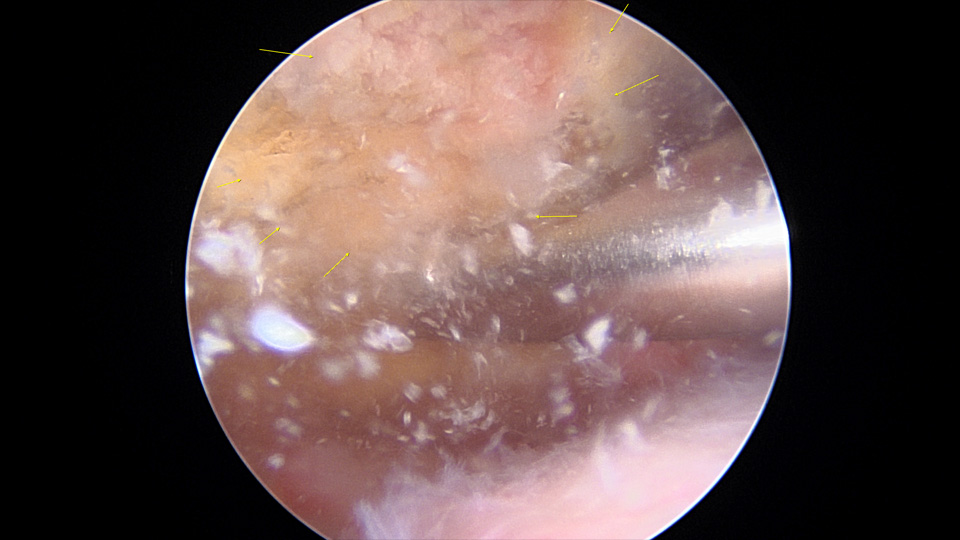

어깨 관절경을 이용해서 석회질을 제거할 수 있다.

- 환자 동의하에 게시된 이미지입니다.